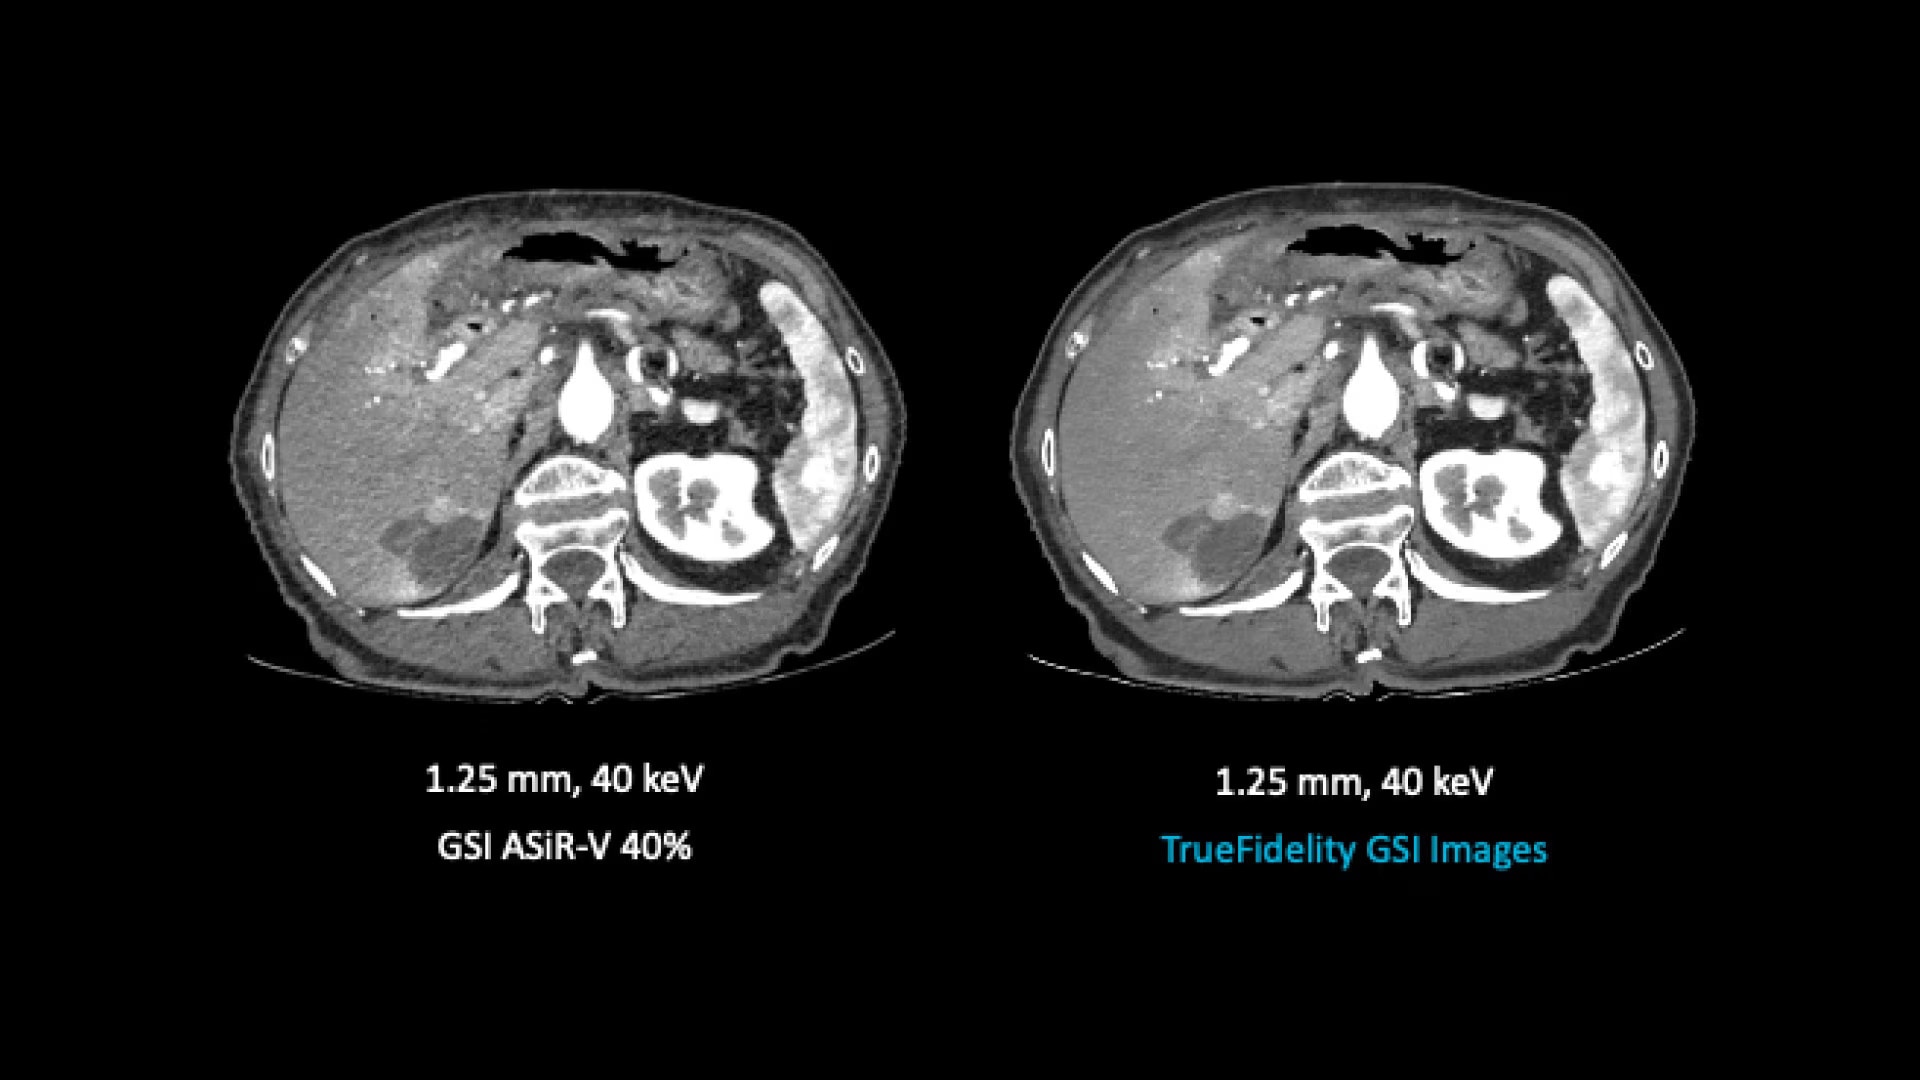

TrueFidelity for GSI now brings the potential to substantially reduce the image noise in all spectral image types

From virtual monochromatic images to material image pairs and virtual non-contrast images, with and without metal artifact reduction. Specifically, reducing the image noise inherent with low keV images resolves one of the traditional technical challenges in adopting more dual-energy protocols across the full patient population.